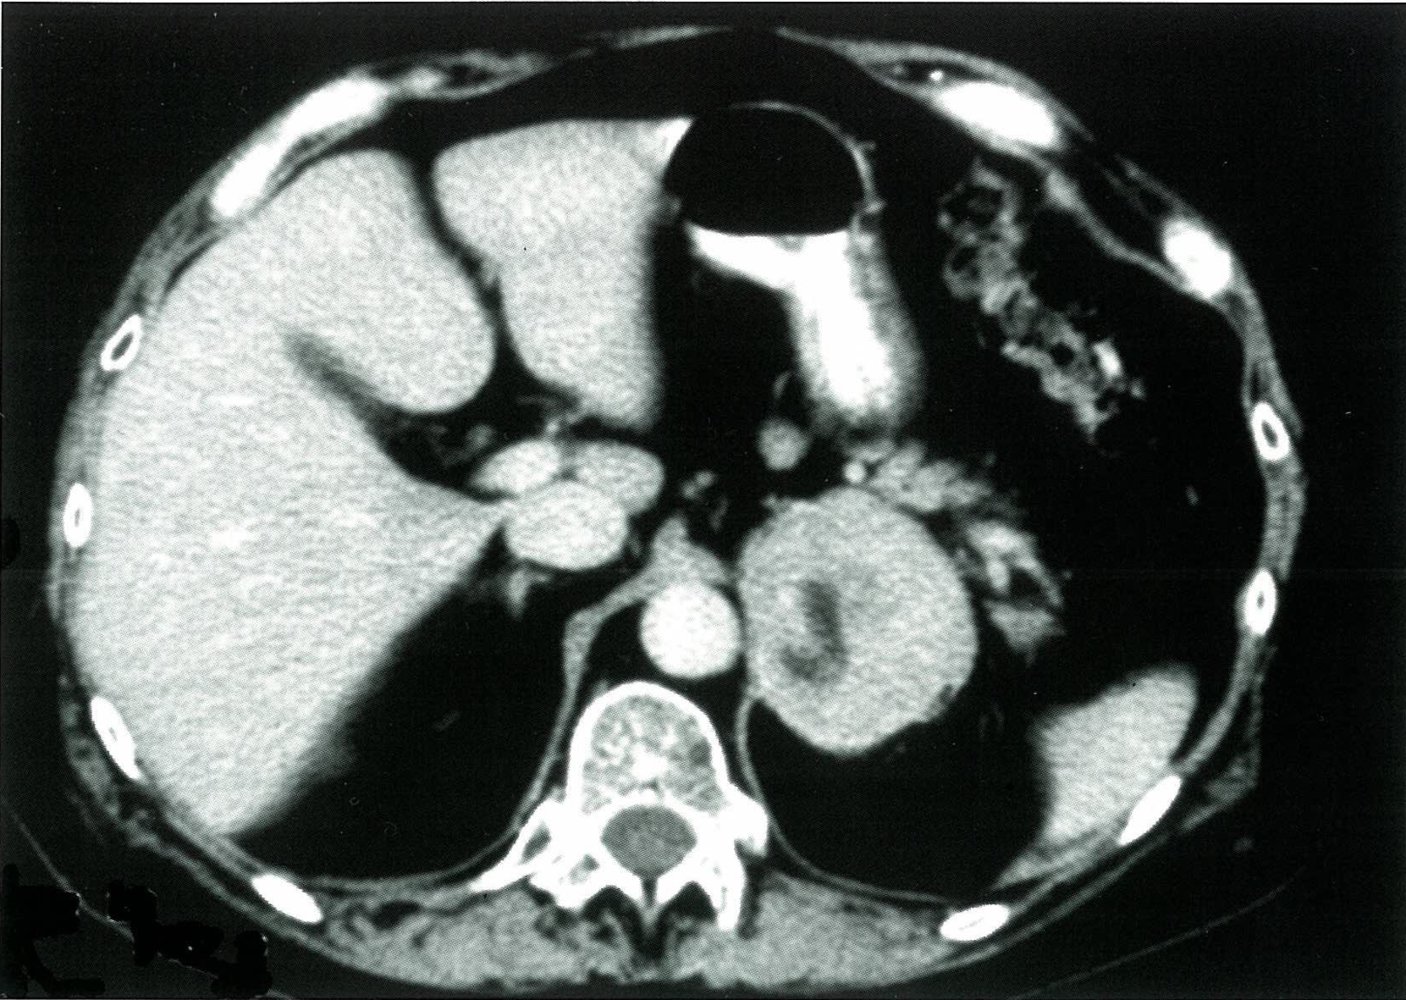

• High-risk features for malignancy include:

• > 10 HU [2]

• β‰₯ 4 cm in diameter [4]

• Heterogeneity

• Irregular tumor margins, necrosis, vascularity, calcification

• High-risk features : Consider surgery (and/or additional imaging).

• Imaging: heterogeneous mass with > 10 HU on CT, > 4 cm in diameter, irregular margins, usually unilateral, possibly necrosis, calcification, or hemorrhage